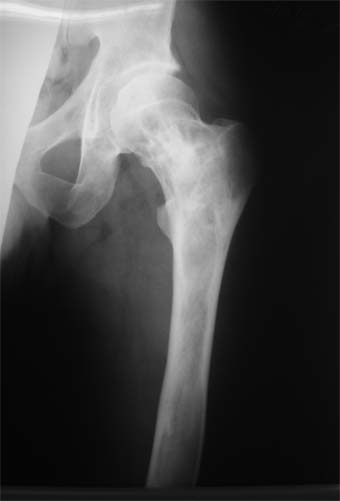

Коллеги!Пациент Д., 35 лет, В 1985 году был поставлен диагноз гемигипоплазия правой нижней конечности. Укорочение 5 см, в 1987 году остеотомия правого бедра, аппарат 4 месяца, удлинили на 2 см из-за нагноения спиц аппарат сняли. В настоящее время Жалобы на дискомфорт, тяжесть в левом бедре, голени при длительной ходьбе, при длительном лежании на левом бедре. Эти жалобы беспокоят втечение 5-6 лет. В 1999 году выявили "изменения" (со слов больного, выписки нет на руках) бедренной кости и костей голени слева. Тогда же предложили в ЦИТО срочно делать какую-то операцию. При осмотре: Правая нижняя конечность. Имеются рубцы на правом бедре по наружной и внутренней поверхностям. Ограничения движений в коленном суставе нет. Кровоснабжение, иннервация сохранены. Левая нижняя конечность. Левое бедро увеличено в объеме, при пальпации пальпируется бедренная кость большего диаметра по сравнению с левым бедром. Пальпация безболезненна. Голень обычной формы. Объем движений в суставах полный. Кровоснабжение, иннервация сохранены. Имеется разница в длине конечностей правая короче на 4-5 см за счет бедра и голени. В приложении вид больного и рентгенограммы бедра 2001 год и 2005 год. Что бы это могло быть? О чем можно думать? Онкология? С уважением Коробушкин Глеб Владимирович Российский государственный медицинский университет кафедра травматологии, ортопедии и ВПХ, доцент

Остеосклеротическая стадия болезни Педжета. Имею двух подобных больных по 15 -20 лет наблюдения. В острой стадии - текли как классическая саркома. "За" - все (рентген+биопсия+клиника) - отправили хоронить, а в результате живы и имеют рентген-картинку похожую Вашей. Поройтесь в минеральном обмене и в почках. Удлинять подобные кости опасно. Можно -биопсию на всякий случай (из зоны склероза и зоны пороза).

У больного полиоссальноая форма фиброзной дисплазии с поражение левой бедренной и большеберцовой кости. На рентгенограммах - тотальное разрастание и остончение кортикального слоя. Имеется удлинение левой нижней конечности на 2,5-3 см за счет голени. Больному показано оперативное лечение левой большеберцовой кости.